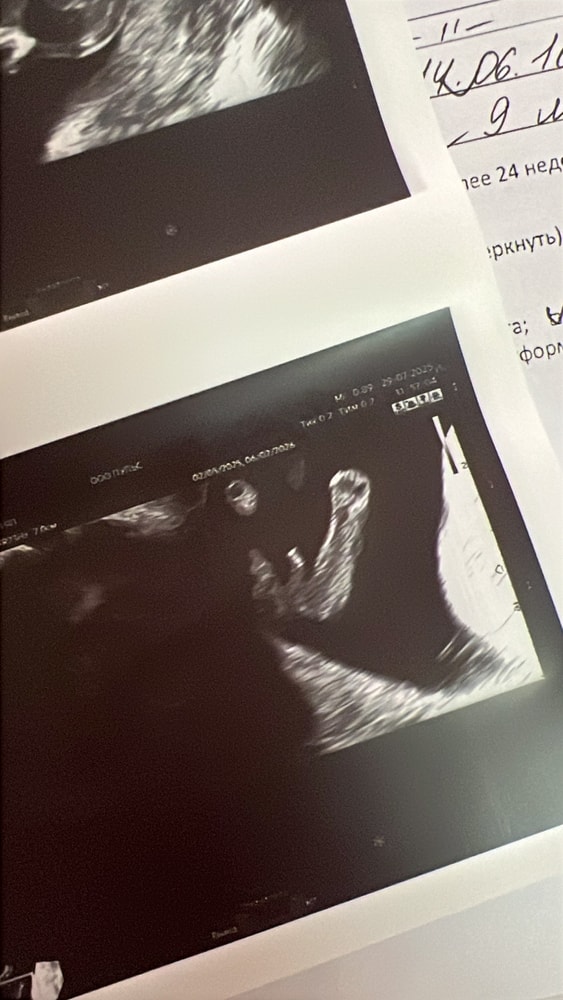

Результаты УЗИНаконец-то я в своей беременяшковой суете добралась рассказать, как у нас дела и как мы растем❤️🥹👶🏻

Малышарик растет🙏чуть опережаем тьфу тьфу срок, кстати выставляют и будут корректировать срок по скринингу, сказано так. Скрининг 1 триместра прошли, все отлично за исключением ВАЖНО кровотоки МПК нарушены ПИ было 2,8 и 2,3. Сразу же приняты оперативно меры по терапии Актовегин, Курантил, Кардиомагнил и Клексан дружно со мной - итог по узи 04.08. кровоток улучшился ПИ 2 и 1,9🙏 далее смотримся 12.08. Риск эклампсии 1 из 4 😬🤪 но с моим анамнезом я не паникую тут главное контроль над ситуацией и стабильность. Спасибо и низкий поклон всей команде врачей РКБ г. Казани, что они с нами на пути к нашей большой мечте - рождению Крохи❤️🙏